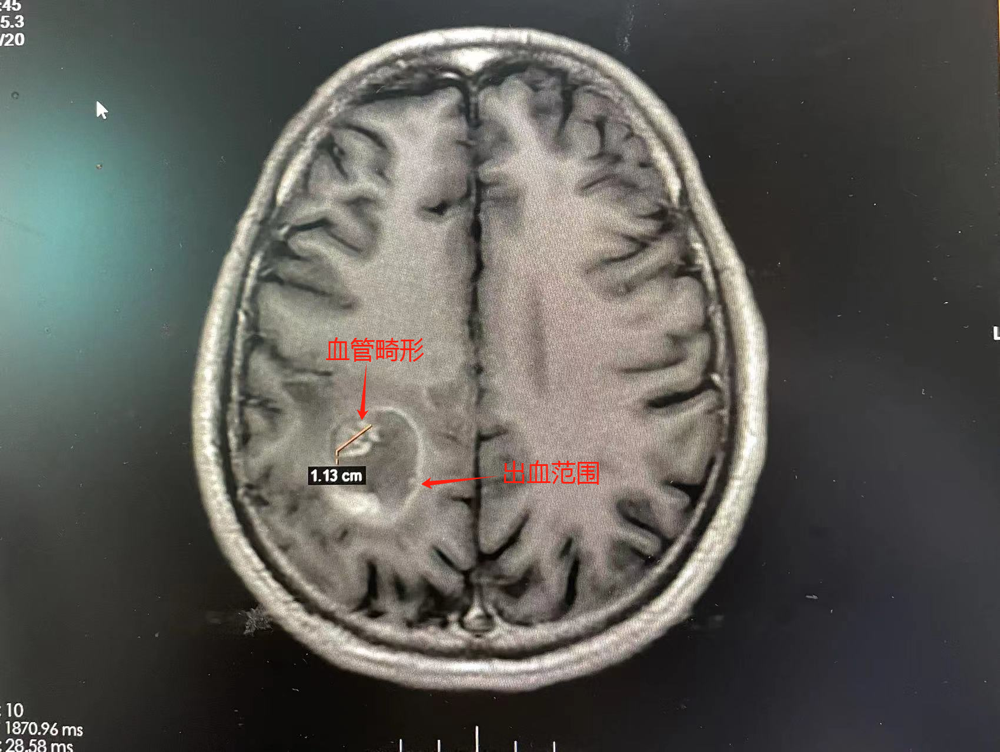

该院副院长、神经外二科主任林涛会诊时,结合影像检查结果,考虑患者右侧顶叶病灶为海绵状血管畸形合并亚急性期出血。“病灶位于脑运动区,出血量大,已经形成明显占位效应,造成脑功能障碍。”林涛表示,如不行手术治疗,血肿持续压迫或增加,很可能会导致脑水肿加重,患者头晕、头痛、左侧肢体乏力会持续加重。

患者MR影像检查